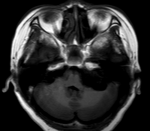

硬膜下出血 現(xiàn)病史【一般資料】男性,50歲,【主訴】突發(fā)左側(cè)肢體無力1周【現(xiàn)病史】以左側(cè)肢體無力為主要表現(xiàn),左側(cè)肢體可抬離床面,行走時跌倒3次,語速減慢,聲音嘶啞,無肢體麻木,無意識障礙,無吞咽困難,無飲水嗆咳,無視物模糊,無明顯頭暈、頭痛,無惡心、嘔吐,無耳鳴等;【既往史】既往高血壓病史50余年,服用降壓藥治療,自訴血壓控制可,冠心病史10年,否認糖尿病病史。【查體】T:36.4℃ ,P:76次/分,R:20次/分,BP:140/90/mmhg。意識清楚,語言尚清楚,語速減慢,眼瞼無下垂,眼球各向活動自如,...